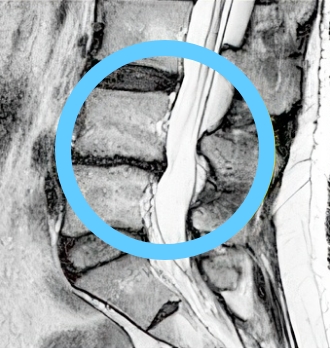

치료 후 탈출된 디스크

10년간 지속적 흡수

탈출된 디스크가 치료 후 10년간 지속적으로 감소, 10년 후에는 약 2/3 가까이 거의 흡수됨

비수술 한방통합치료 치료 10년 후

탈출된 디스크가 흡수된 모습

치료 전 (2007)

10년 경과 (2018)

※ 환자분에게 사전 동의를 받아 동일 조건에서 촬영되었으며, 개인에 따라 치료 후 부작용이 발생할 수도 있으니 의료진과 상담 후 치료를 진행하시기 바랍니다.